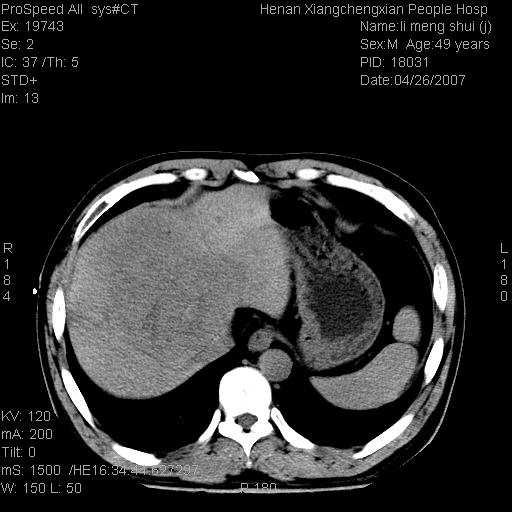

| 患者,男,49岁, 腹疼伴恶心\\呕吐20天,20天前无明显诱因出现右上腹部疼痛,钝疼,无放射,伴恶心\\呕吐,不伴发热.患者不愿增强. b超:肝脏右叶实性占位. ct:肝脏右叶可见一巨块状圆形低密度影,大小约93mm*84mm,其内可见点状高密度影,胆囊、胰腺、脾脏大小、形态及密度未见异常,腹膜后间隙未见肿大淋巴结影。 印象:肝脏右叶巨大肿块,性质待定,建议增强并穿刺活检进一步确诊。 ct平扫: ![]() ![]() ![]() ![]() ![]() ![]() ![]() ![]() ![]() ![]() ![]() ![]() ![]() ![]() ![]() ![]() ![]() 肝脏右叶肿块ct引导下穿刺活检术 患者于16时05分仰卧于ct检查台上,首先行肝脏ct扫描确定进针位置、深度、角度。在局麻下行ct引导下肝脏右叶肿块穿刺活检术。常规消毒、铺巾、局麻。在ct引导下使活检针经右侧腋中线、第9肋间隙垂直胸壁进针90mm,针头进入病变预定位置。在病变预定位置多点、多方向抽取小米样病变组织多块,涂片五张送病理检查。术后穿刺点局部无出血,未出现腹腔积液等并发症。术中及术后患者生命体征稳定,手术于17时10分成功完成。患者安返病房。 穿刺片 ![]() ![]() ![]() ![]() ![]() ![]() ![]() ![]() ![]() ![]() ![]() ![]() ![]() ![]() ![]() ![]() 病理结果肝细胞癌 ![]() 原贴地址:http://www.radinet.com.cn/forum_view.asp?forum_id=4&view_id=24130 ok |